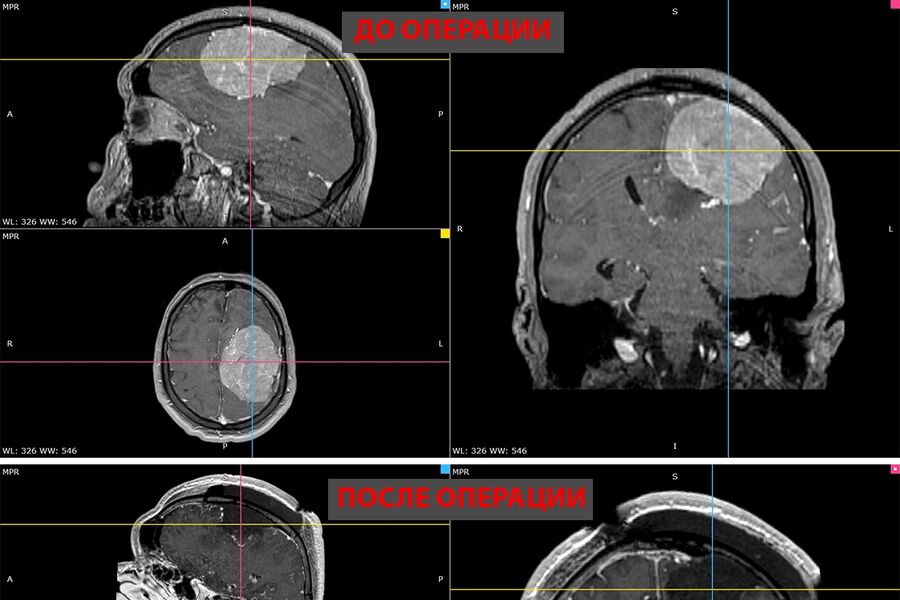

В ноябре прошлого года у мужчины появилась слабость в правой руке и затруднения речи — МРТ выявила у него менингиому диаметром более восьми сантиметров в левом полушарии мозга. К концу года рука практически перестала работать, ходьба давалась пациенту с трудом.

Пятичасовая операция прошла успешно. Опухоль удалили полностью. Уже на следующий день появились движения в руке, через две недели пациент снова стал сам ходить. У него восстановились речь и движения, приступы исчезли.